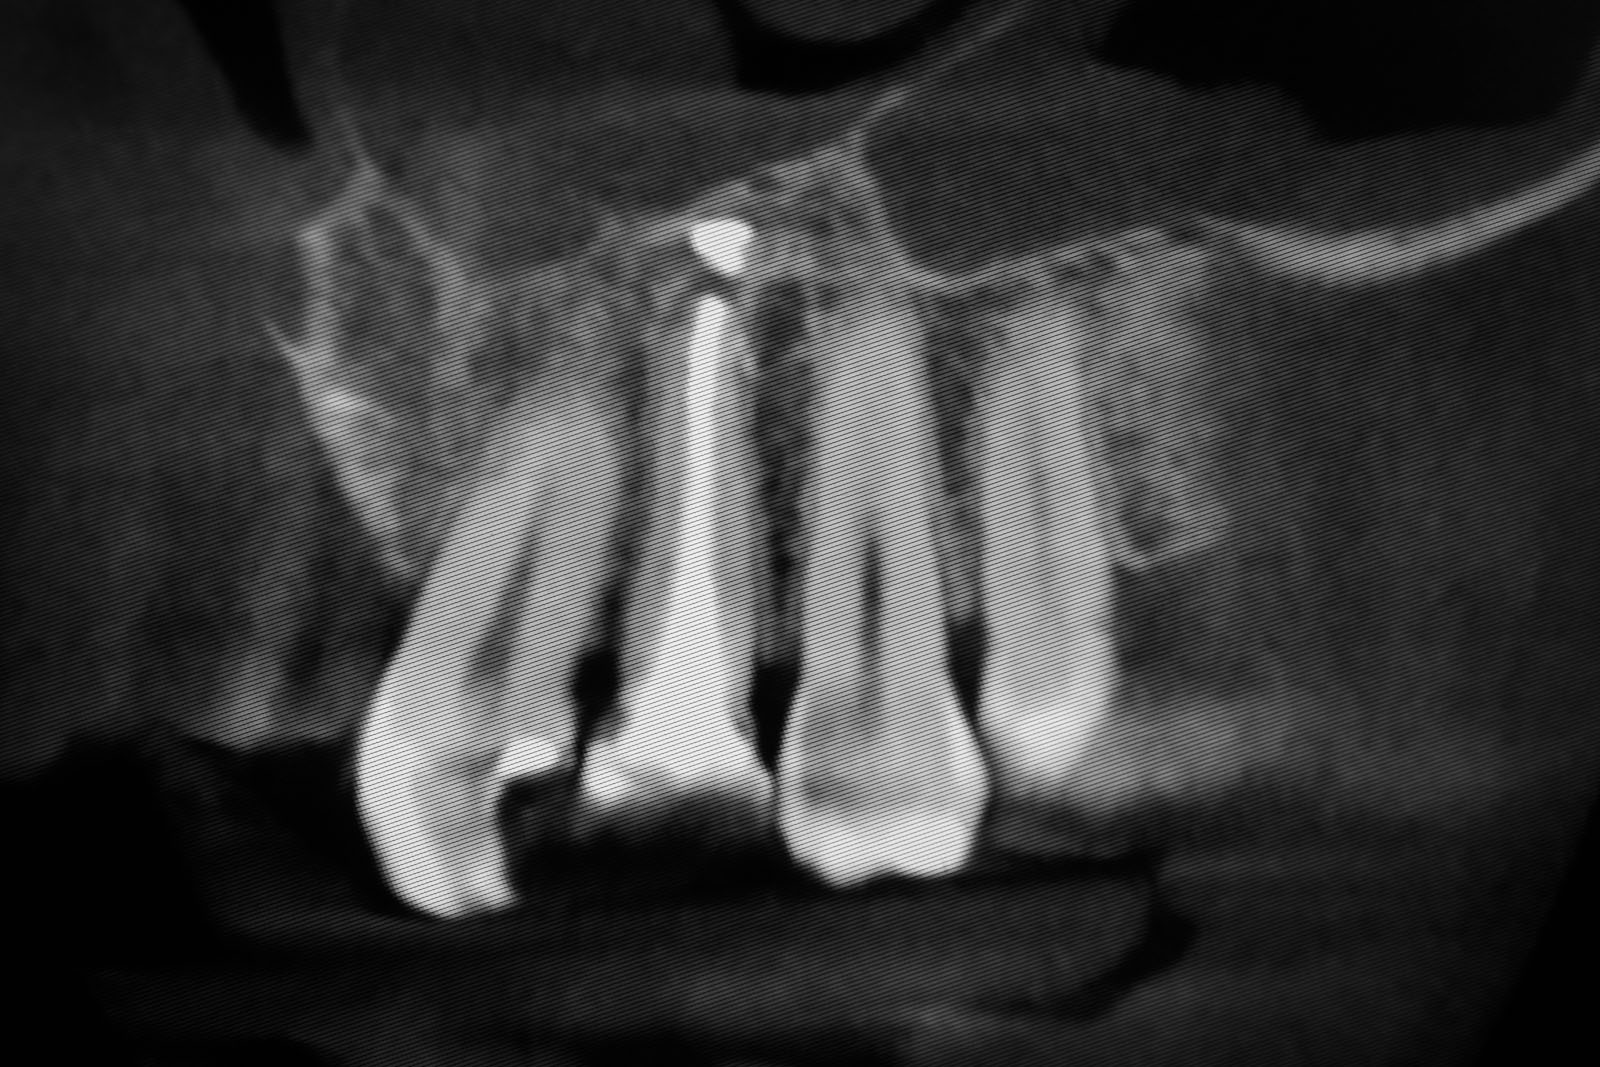

Przed podjęciem leczenia należy określić stopień zaniku kości szczęk oraz żuchwy. W tym celu przeprowadza się badanie kliniczne oraz odpowiednią diagnostykę obrazową pacjenta. Uwzględnia ona zdjęcie panoramiczne OPG jako podstawę dwuwymiarowego obrazowania podłoża kostnego oraz możliwe jest badanie tomograficzne CT lub bardziej precyzyjna tomografia stożkowa CBCT. Opcjonalnie wykorzystywana diagnostycznie tomografia pozwala na bardziej wnikliwą ocenę stopnia zaniku kości w trójwymiarowym, przestrzennym obrazie.